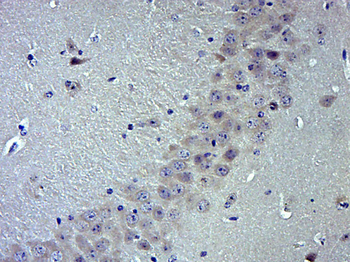

Immunohistochemical staining of human colon cancer using TRPV1 antibody